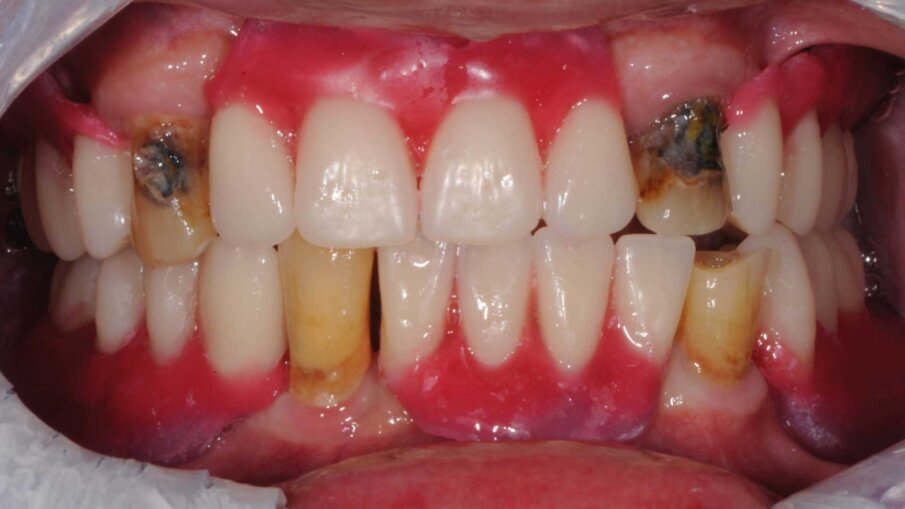

Il paziente si presentò alla nostra osservazione lamentando una diminuzione della capacità masticatoria. All’osservazione clinica e radiografica (Figg. 1, 2) si evidenziava la mancanza di numerosi elementi dentari e di una diffusa malattia parodontale, il tutto complicato dalla presenza di carie destruenti su tutti gli elementi dentari con migrazione degli stessi. Lo spostamento dei denti aveva portato a perdita della dimensione verticale e di tutti i punti di riferimento per la ricostruzione della dentatura.

Al paziente fu spiegato che la strategia migliore consisteva nell’estrazione di tutti gli elementi dentari e l’inserimento di sei impianti in ogni arcata dentaria e successivamente il ripristino delle arcate con due protesi tipo Toronto. Si decise di non estrarre subito i quattro canini perché sarebbero serviti per stabilizzare le mascherine chirurgiche durante la chirurgia. Lo studio del caso e la sua realizzazione fu fatta con metodo analogico. Due modelli in gesso furono montati alla giusta dimensione verticale e fu realizzato il montaggio dei denti per visualizzare il risultato finale (Fig. 3). Dal montaggio dei denti furono realizzate le mascherine chirurgiche che sarebbero state utilizzate per gli esami radiografici tridimensionali e avrebbero guidato il posizionamento degli impianti durante la chirurgia. All’esame radiografico tridimensionale (Figg. 4-7) si notava la presenza di una quantità esigua di osso coronalmente ai seni mascellari e al nervo alveolare inferiore. Si decise di inserire impianti extracorti 4,5 mm di lunghezza in queste zone, per evitare sia impianti inclinati sia cantilever molto estesi. Lo studio della scala dei grigi, o scala Hounsfield, mostrava una densità ossea tale da consentire il carico immediato anche in queste zone. Ovviamente sarebbe stata necessaria la conferma intra-operatoria valutando clinicamente la compattezza dell’osso tramite la fresatura.